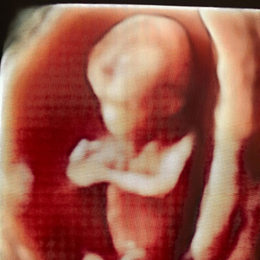

Ecografía del corazón fetal en 4D

Ocho de cada mil bebes nace con algún defecto cardíaco congénito. Estas anomalías se producen por un desarrollo anormal del corazón durante el embarazo y pueden consistir en defectos de sus paredes o válvulas, o de los vasos sanguíneos que entran o salen de él.